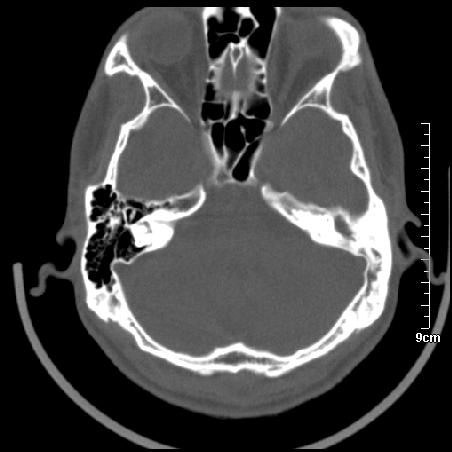

病例2

m/27

胆脂瘤是是以鳞状上皮内衬充满角质化碎片的囊,随着角化屑片的不断堆积,肿块逐渐增大,胆脂瘤可为先天性(2%)或后天性(98%)。胆脂瘤有感染史。中耳内的鳞状上皮通常有外耳道的上皮通过一鼓膜的缺损移行至中耳,其他的原因包括鳞状上皮化生。由于欧氏管的功能不全所引起的中耳负压可产生上鼓室鼓膜松弛部的牵引性开袋。继而发展成胆脂瘤。成年人胆脂瘤时乳突常发育差,而儿童常有广泛性乳突气化,这种气化可导致胆脂瘤的更广泛的乳突扩散。后天性胆脂瘤患者大多数存在骨质破坏。

松弛部胆脂瘤有中央性穿孔或后上部牵引口袋所致。紧张部胆脂瘤经常侵蚀听小骨并引起传导性耳聋。

中耳胆脂瘤有两个重要并发症:一是面神经管的水平段受暴露,二是外侧半规管受侵蚀产生瘘管。面神经在ct上难以显示或不可能显示,除非其周围有空气包绕或有良好轮廓的骨性覆盖。胆脂瘤还可合并感染,产生于急性中耳炎.乳突炎所描述的那些合并症。

左侧慢性中耳炎伴胆脂瘤形成。

左中耳乳突炎合并胆脂瘤形成